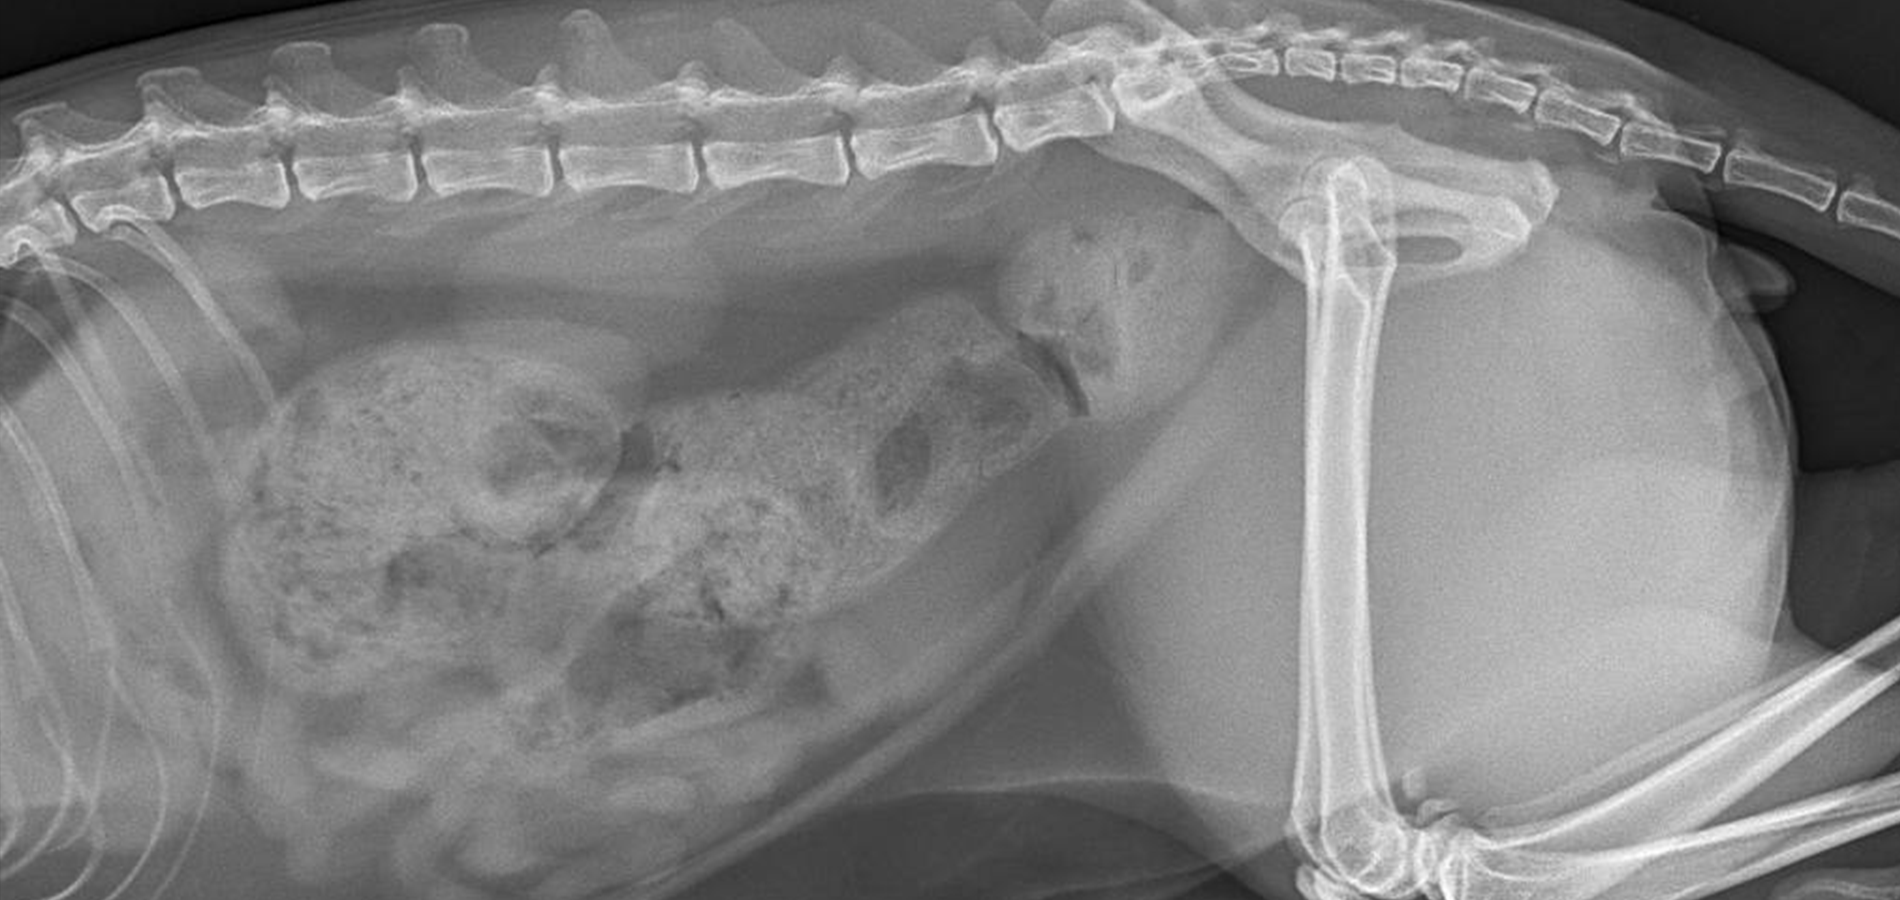

(кот 3,5 года: отсутствие стула в течение 5-ти дней)

Основной метод диагностики копростаза – это рентген брюшной полости. Рентгенография позволяет определить наличие переломов, аномалий в строении, наличие инородных тел в просвете кишки, визуализировать рентгеноконтрастные новообразования в брюшной полости и кишечнике.